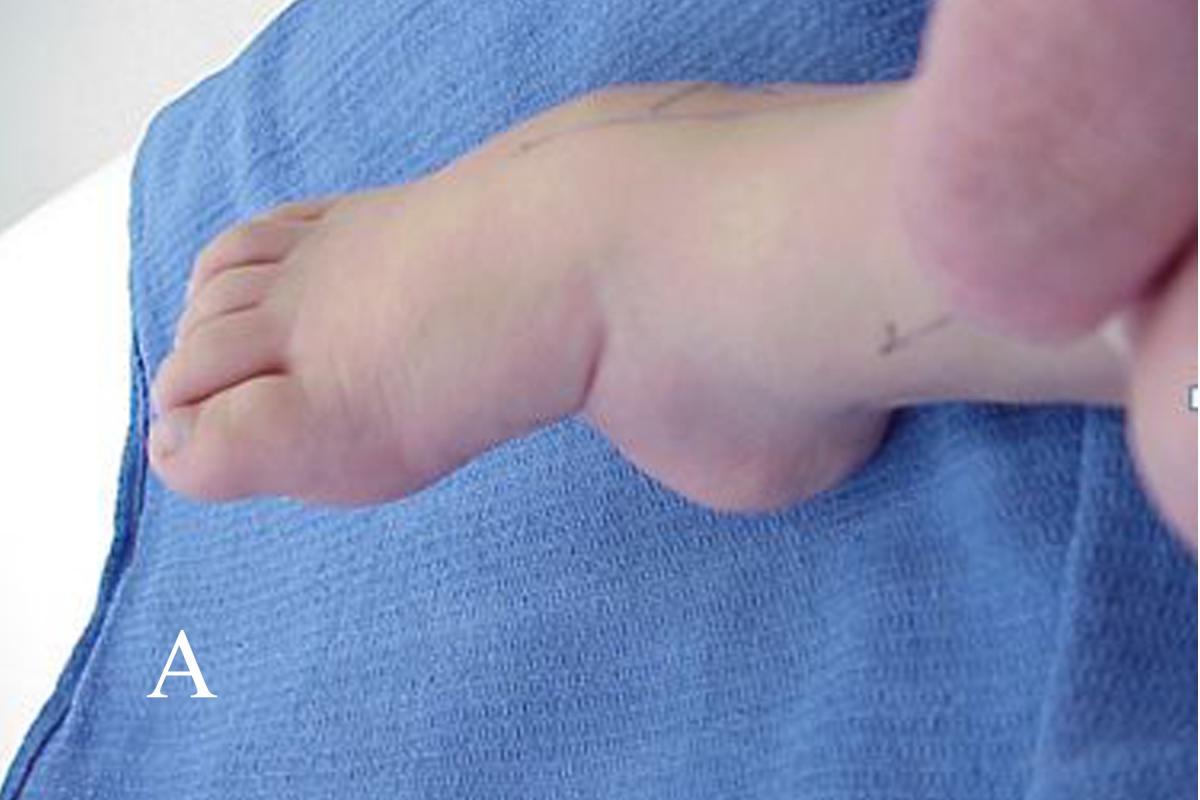

Ponseti also recognized an atypical form of talipes equinovarus. The major features of atypical talipes equinovarus are plantarflexion of both medial and lateral columns, short foot, rigid equinus, a deep plantar and medial midfoot crease, and a deep crease above the posterior heel. He considered these to be resistant, some syndromic, others teratologic, some neurogenic and occasionally iatrogenic. He modified the manipulation and casting protocol for these feet.

Fourth, until one has correctly aligned the forefoot and rearfoot, it is inappropriate to treat ankle equinus. Doing so has several undesirable consequences. Casting an unyielding equinus deformity will eventually damage the talar trochlear surface, making it flat and causing it to lose its sphericity. Ankle dorsiflexion will be mechanically limited. Rocker bottom deformity results from attempting to dorsiflex the rearfoot prematurely against the unyielding tendo-Achilles. Inflexible equinus causes the midfoot to dorsiflex against the rearfoot along the lateral column while the calcaneus remains in a plantarflexed position. This breaches the foot through the calcaneocuboid joint as well as the fourth and fifth metatarsal cuboid articulations.